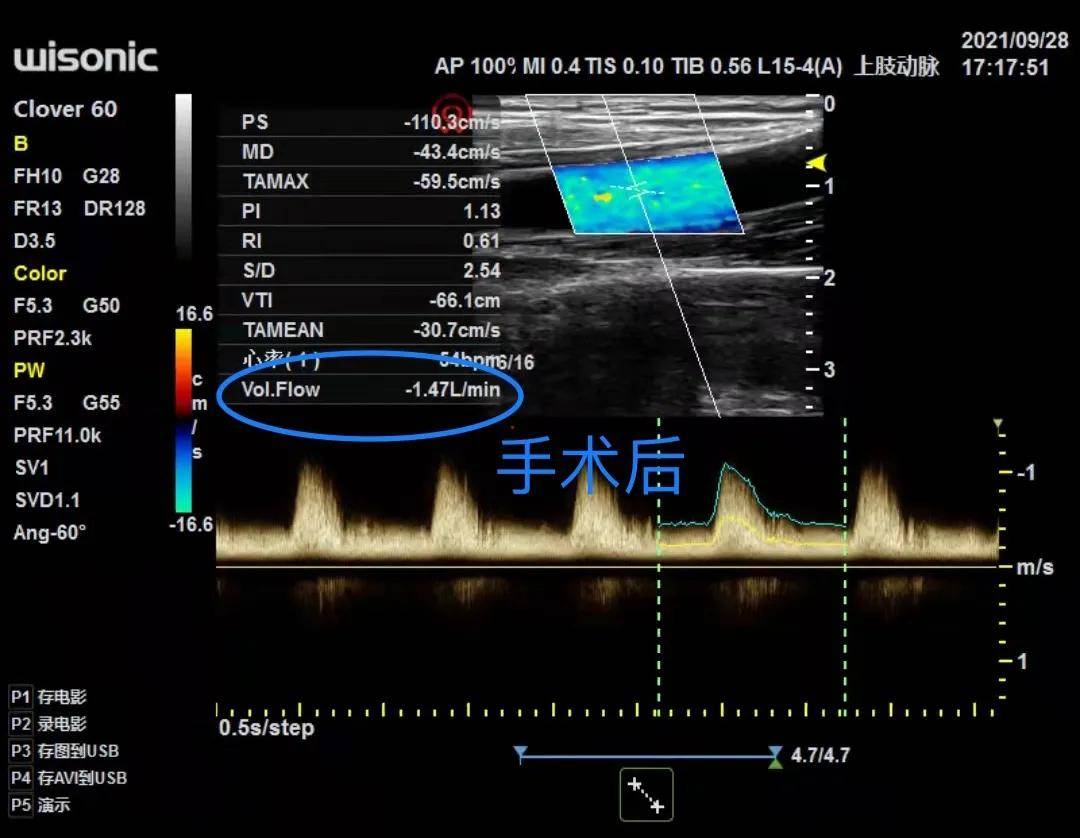

患者李某 , 男 , 尿毒症 , 于西安市第三医院血透室进行规律透析 。 1月前 , 李某发现自己浑身无力 , 食欲不振 , 但未曾未引起重视 。 随后在刘绥军主任查房时发现其精神状态不佳 , 通过听诊、触诊发现患者李某内瘘狭窄 。 经彩超评估后发现李某内瘘狭窄处血管仅有1.4mm , 肱动脉流量0.35L/min 。 结合其当天实验室检查指标透析前肌酐606mmol/l , 透析后肌酐366mmol/l , 综合分析考虑内瘘狭窄严重影响了透析充分性 , 造成患者身体状态不佳 。

9月28号下午 , 手术在血透室手术室进行 。 刘绥军主任亲自主刀 , 史井波医生协助行内瘘重建术 。 手术顺利完成 , 术后史井波医生再次超声评估显示患者李某内瘘通畅 , 血管内流量达1.47L/min 。 患者李某悬着的心也落地了 , 脸上出现久违的笑容 。